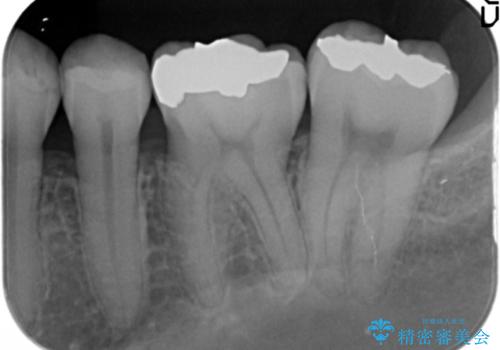

- 笑った時に見える下顎の銀歯を白くしたいと希望され来院されました。

銀歯を丁寧に外したのち、セラミックインレーによる修復を計画します。